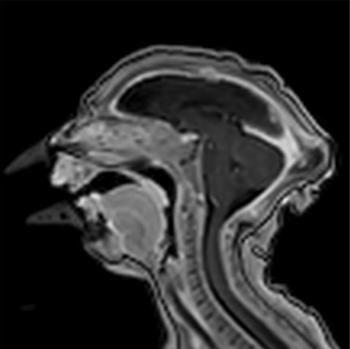

Figure 4. Images obtained in the case of an 18-year-old woman, first seen for rash at 10 weeks of pregnancy, with confirmed Zika virus infection. US findings obtained at 20 weeks of gestational age were reportedly normal, with normal head circumference of 17.5 cm. At 37 weeks of gestational age, (a) sagittal transvaginal and (b) coronal transabdominal US images obtained with the head upside down show a small head circumference (26.4 cm, corresponding to 28 weeks 5 days, below the 3rd percentile), moderate ventriculomegaly with dense intracranial calcifications (arrowheads on a), and abnormal head shape with flattened appearance and thickened skin (arrow on a). On the sonogram, it is difficult to precisely localize the calcifications, given the thin parenchyma. (c, d) Axial bone window CT images, (e) sagittal localizer CT image, and (f–h) axial CT images show microcephaly with cerebral atrophy, and, despite ventriculomegaly, the extra-axial cerebrospinal fluid spaces are still prominent. The hypoattenuating calcifications are predominantly located in the subcortical white matter at the gray matter–white matter interface. There is markedly abnormal skull shape with some eversion of the bones at the suture sites (particularly frontoparietal sites), with redundant skin folds (particularly in the parieto-occipital region). (i) Sagittal T1-weighted, (j, k) coronal T2-weighted, and (l) axial susceptibility-weighted MR images obtained at 1 month of age show an undersegmented midbrain, severe microcephaly, open sylvian fissures, and polymicrogyria. The dense calcifications are evident on the susceptibility-weighted image. On the sagittal images (a, e, i), note the small supratentorial compartment and associated skull deformity.

Figure 6. Images obtained in the case of a 24-year-old woman pregnant with twins, with characteristic rash at 9 weeks of pregnancy and confirmed Zika virus infection. (For each pair of images, the first image is of twin A, and the second image is of twin B.) At 14 weeks of gestational age, the fetal head size of both twins was normal. The head size never went below the 3rd percentile for either fetus in examinations at 19–28 weeks. (a, b) Sagittal and (c, d) axial fetal MR images were obtained at 36 weeks. (e, f) Axial and (g, h) surface reconstruction postnatal CT images and (i, j) axial T2-weighted and (k, l) coronal MR images were obtained 1 week after delivery at 38 weeks of gestational age. There is severe microcephaly with profound frontal lobe hypoplasia. Calcifications in the subcortical white matter at the gray matter–white matter junction are visualized. Both twins have a flattened appearance of the pons. The spinal cord is atrophic (best seen on a). Redundant skin is seen in the occipital region. There is polymicrogyria involving the frontal and parietal regions and atrophic cortex and white matter in the occipital regions. Each twin has hypoplasia of the corpus callosum, with prominent fornices. There is abnormal myelination in the occipital region that, in twin A (i), has the appearance of a cyst or septation within the ventricle. The cerebellum is somewhat small and nodular. There is lack of rotation of the hippocampi.